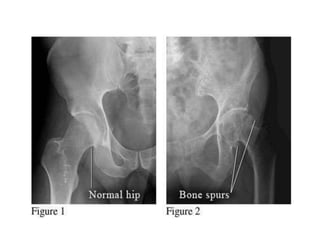

RADIOLOGIC FINDINGS OF OA

• Narrowing of joint space

(due to loss of cartilage)

• Osteophytes

• Subchondral (paraarticular) sclerosis

• Bone cysts

X-RAY OF HIP OA

• X-ray shows

osteophytes,

subchondral

sclerosis, and

complete loss of joint

space

• Patients often

present with deep

groin pain that

radiates into the

medial thigh

Hip Joint

RADIOLOGIC FINDINGS OFOA • Narrowing of joint space (due to loss of cartilage) • Osteophytes • Subchondral (paraarticular) sclerosis • Bone cysts

• X-ray shows osteophytes, subchondral sclerosis,and complete loss of joint space • Patients often present with deep groin pain that radiates into the medial thigh Hip Joint